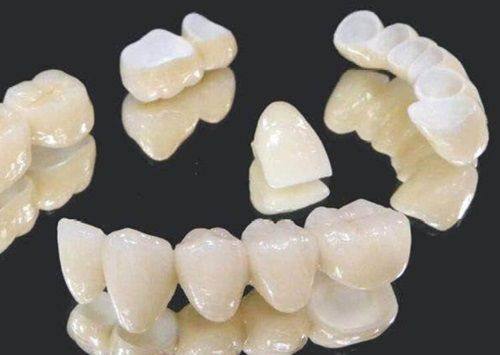

规范的牙冠修复是更关键的一环。选择正规的口腔医疗机构、经验多的牙医制作的牙冠,能够确保牙冠的密合性和贴合度,避免出现边缘渗漏导致的继发感染,同时牙冠的材料需要符合后牙的咀嚼强度需求,比如金属烤瓷冠、全瓷冠都可以满足后牙的使用要求,患者可以根据自身的经济情况和美观需求进行选择。